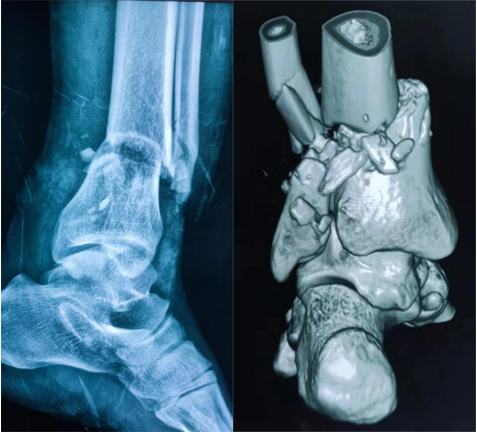

抱着最后的希望邓先生被送到了骨二科,医务人员立即予以开通绿色通道急诊完善术前检查。检查中李杨发现,邓先生伤口在小腿远端,踝关节上方呈环形离断,整只脚畸形仅有部分表皮相连,胫腓骨均粉碎性骨折,还有大量骨质及皮肤缺失,肌肉、肌腱均已断裂,断端完全失去血运,无法活动,更没有知觉,并且伤口周围全是煤灰,污染严重。已经疼得快要休克的邓先生,被紧急送往手术室。

在骨二科医务人员的精心照料下,邓先生伤情很快好转,目前患者断端血运已恢复,皮肤颜色从苍白变为红润,脚趾头已可自主屈伸活动,术后复查患者X线片显示,骨折复位、固定良好。“由衷地感谢湘南学院附属医院骨二科,感谢李杨主任及全体医护人员,挽救了我的断肢。”邓先生激动地说。